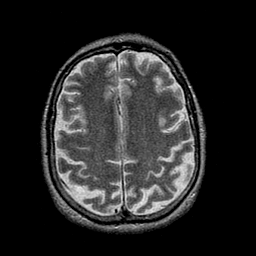

Alzheimer's disease: overlay -- Slice #36

[Home][Help][Clinical] Slice 36